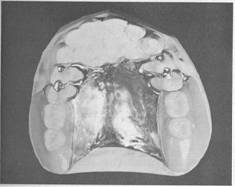

Fig. 5-37 A, Maxillary major connector in the form of palatal linguoplate with provision for attaching full­coverage acrylic resin denture base. B, Completed removable partial denture with acrylic resin base. Palatal linguoplate is supported by rests occupying lingual rest seats prepared in cast restorations on canines. This type of removable partial denture is particularly applicable where (1) residual ridges have undergone extreme vertical resorption and (2) terminal abutments have suffered some bone loss and splinting cannot be accomplished.

extends to the junction of the hard and soft palates (see Fig. 5-36). The other method is to use a cast major connector anteriorly, with retention posteriorly, for the attachment of a resin denture base that extends posteriorly to the anatomic landmarks previously described (see Fig. 5-37).